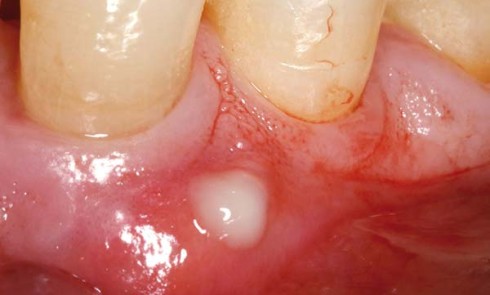

Article réservé à nos abonnés La prise en charge en urgence de l’abcès parodontal

1. Diagnostic L’abcès parodontal correspond à une inflammation purulente, le plus souvent aiguë et localisée, entraînant une destruction rapide des...